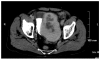

Solitary fibrous tumor (SFT) is a rare mesenchymal neoplasm which may be found everywhere in the body. It is now distinguished into two forms, pleural and extrapleural, which morphologically resemble each other. Abdominal localizations are quite rare, with 10 cases only reported in bladder; rarely they can be source of paraneoplastic syndromes (i.e., hypoglycemia secondary to insulin-like growth factor). In April 2006 a 74-year-old white male presented with chills, diaphoresis and acute abdominal pain with hematuria. At admission in emergency he underwent an abdominal Xray (no pathological findings) and an ultrasound examination of the kidneys and urinary tract, which revealed a pelvic hyperechogenic neoformation measuring approximately 10×8×7 cm, compressing the bladder. Blood chemistry at admission revealed only a mild neutrophilic leucocytosis (WBC 16600, N 80%, L 11%), elevated fibrinogen and ESR, and hypoglycemia (38 mg/dL). Macro scopic hematuria was evident, while urinocolture was negative. Contrast enhanced CT scan of the abdomen and pelvic region revealed a large round neoformation dislocating the bladder, with an evident contrast-enhanced periphery and a central necrotic area. Continuous infusion of glucose 5% solution was necessary in order to maintain blood glucose levels above 50 mg/dL. The patient underwent complete surgical resection of an ovoidal mass coated by adipose tissue, with well delimited margins; histological findings were consistent with solitary fibrous tumor (SFT). Hypoglycemia resolved completely with removal of the growth. In this case report we describe a SFT growing in the bladder, a quite rare localization, which presented a unique hypoglycemia. In contrast to the majority of cases reported in the literature, the behavior of this SFT was not aggressive, and, since the patient is still alive, surgical resection was considered conclusive.